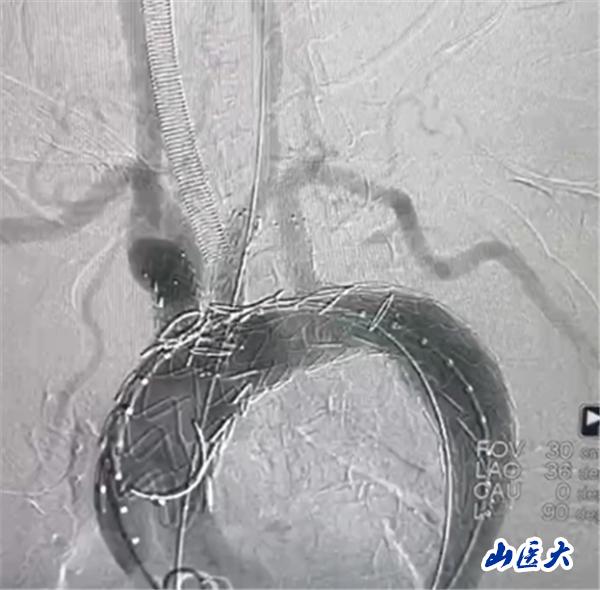

首例患者是一位55歲的女性,她患有高血壓約2年時間,平時也會規律服用多種降壓藥,但血壓控制始終不盡人意。2023年4月下午,她出現不明原因的頭痛,在家拔罐緩解少許便未到醫院就醫,次日凌晨突感胸悶、胸背疼痛伴有呼吸困難等癥狀、家人急忙撥打了120,把患者送入醫院急診科進行救治,醫生在急診科行胸腹主動脈CTA時,顯示主動脈弓部-降主動脈及腹主動脈壁間血腫,遂收治入醫院血管外科,患者入院10天后復查血腫仍未有改善,依然伴有胸背部疼痛等不適,如不進一步處理,可能發展為夾層危及生命,患者及家屬經過與醫生團隊了解溝通,決定進行創傷小、恢復快的介入手術治療。張瑋教授、符偉國教授、董紅霖教授及其血管外科團隊(閆盛、常文凱、田琴琴)共同商討手術方案,最終確定使用Zipper?一體式主動脈弓覆膜支架系統,行胸主動脈覆膜支架腔內隔絕術+無名動脈、左頸總動脈、左鎖骨下動脈分支重建術為患者進行治療。董紅霖教授及其血管外科團隊根據患者術前頭顱CT平掃提示雙側側腦室旁缺血灶,血壓控制不穩定,屬夾層壁間血腫非典型夾層等風險點,制定了完整的手術方案,術中經股動脈置入Zipper支架主體,經預留導絲超選無名動脈,并確保主體支架對位準確,順利置入左頸總動脈、左鎖骨下動脈支架,重建弓上三分支。手術過程非常順利。術后觀察主動脈及分支覆膜支架定位準確;無內漏;分支支架通暢,動脈供血正常。

術中造影結果

術后效果